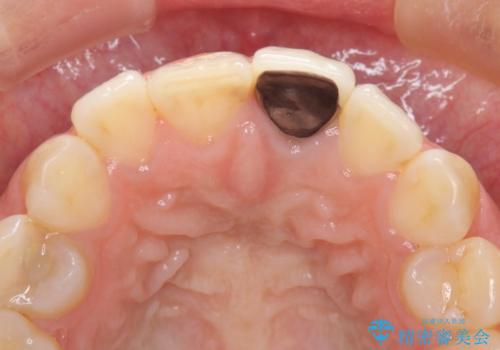

- 前歯をメタルの被せものにしており、セラミックに変えるのを希望された患者様です。

土台も金属だったため、歯がかなり黒く変色していました。

色は完全にとるのが不可能であることをご了承頂いた上で、土台と被せものの治療を行いました。

今回は歯自体が黒くなって歯茎から透けて見えている黒ずみのため、セラミック治療で改善させることは困難だというお話をしました。その上でできる範囲できれいに治療することになりました。